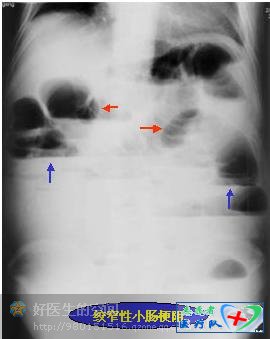

绞窄性小肠梗阻:表现为梗阻近段肠曲扩张、积液多、积气少(红箭头),即表现为腹腔内有较多的小气液平面(蓝箭头),空、回肠转位,可见“假肿瘤”征——即两端闭锁的绞锁肠段内充满大量液体,致使仰卧前后位片上呈肿块影,而站立位或侧卧水平位片上则在该肿瘤块影上部见一短小的液面。